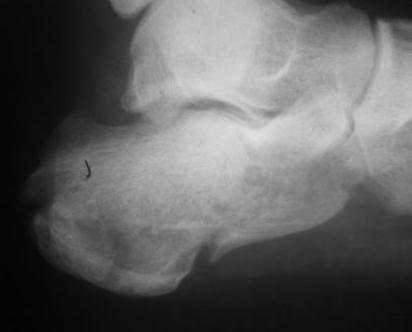

Re: перелом пяточной кости